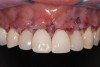

Fig 10. Final smile.

Figure 10

After healing (Figure 7), previous restorations were removed (Figure 8) and the existing preparations were modified; the laterals and canines were also prepared for veneers to the ideal biological position. Pigmented dentin (resulting from tetracycline use) was exposed once the previous restorations were removed, and the new preparations were finalized.

“Masking buildup” was performed (Figure 9), according to the concepts of immediate dentin sealing.14 A slightly opaque veneer composite cement was used for cementation and to enhance the masking effect (Figure 10).